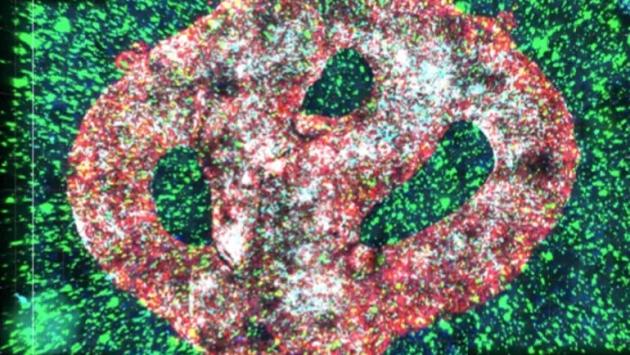

Дослідники з Південної Кореї запропонували новий підхід до імунотерапії солідних пухлин. Він дозволяє безпосередньо всередині організму перетворювати пригнічені пухлиною імунні клітини на активні протипухлинні, повідомляє Phys.

У багатьох пухлинах уже присутні макрофаги — імунні клітини, здатні знищувати рак. Проте середовище пухлини блокує їхню активність, позбавляючи ефективності природний імунний захист.

Команда Корейського передового інституту науки і технологій (The Korea Advanced Institute of Science and Technology, KAIST) під керівництвом професора Джі-Хо Парка з кафедри біо- та нейроінженерії запропонувала спосіб подолати це пригнічення. Вчені розробили терапію, яка перепрограмовує макрофаги безпосередньо в пухлині, перетворюючи їх на CAR-макрофаги.

Метод, деталі якого опубліковані в журналі ACS Nano, ґрунтується на введенні препарату прямо в пухлину. Макрофаги поглинають ліпідні наночастинки, що містять мРНК для синтезу CAR-білків і додаткові імуностимулятори.

У результаті клітини починають самостійно виробляти рецептори розпізнавання раку. Так макрофаги стають активними протипухлинними клітинами, здатними не лише поглинати ракові клітини, а й запускати імунну відповідь навколо себе.

Щоб уникнути цих обмежень, дослідники зосередилися на пухлинно-асоційованих макрофагах, які вже накопичуються в зоні пухлини. Ліпідні наночастинки спеціально сконструювали так, щоб вони легко поглиналися саме цими клітинами.